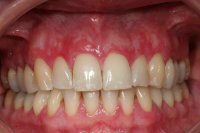

Gingival hälsa på intakt och reducerat parodontium.

Parodontal stabilitet karakteriseras av framgångsrik behandling genom kontroll av lokala och systemiska riskfaktorer, vilket resulterat i

• minimal blödning vid sondering (BVS < 10 % av tandytorna)

• fickdjup < 3 mm

• ingen progressiv parodontal nedbrytning/vävnadsförlust

• optimal förbättring i övriga kliniska parametrar hos behandlad parodontitpatient.